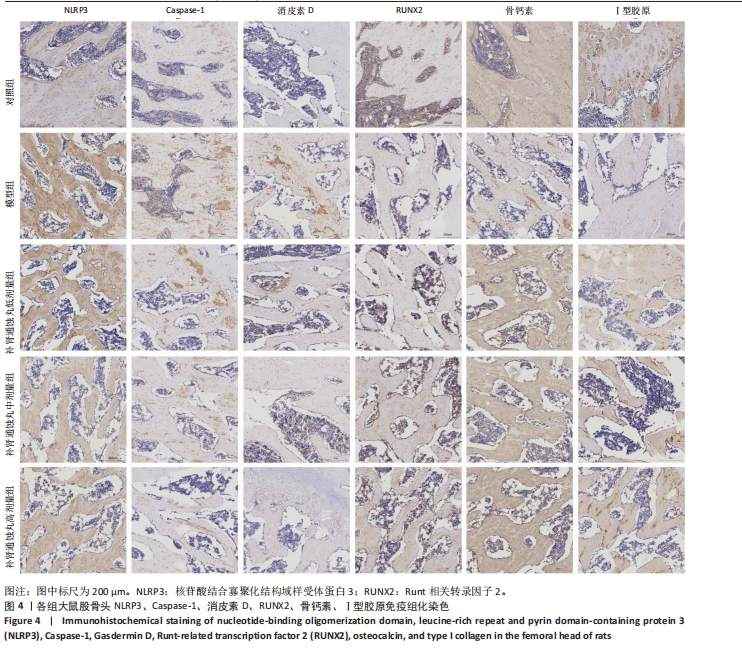

.1 实验动物数量分析 参加实验SD大鼠数量为50只,均进入结果分析。 2.2 Micro-CT检测结果 通过Micro-CT观察各组大鼠股骨头区域骨质变化,见图1。乙醇会导致大鼠股骨头软骨下骨骨量明显减少,骨小梁排列出现紊乱、稀疏等状况,而补肾通蚀丸能够改善上述情况,且呈现一定的剂量效应。模型组骨小梁厚度、骨小梁数目、骨体积分数、骨密度较对照组显著降低(P < 0.01),模型组骨小梁间隙较对照组则显著升高(P < 0.01)。经过不同剂量补肾通蚀丸干预后,各项指标均出现不同程度的逆向改变;其中,与模型组比较,补肾通蚀丸高剂量组骨小梁厚度、骨小梁数目、骨体积分数、骨密度均显著升高(P < 0.05),骨小梁间隙则显著降低(P < 0.05);与模型组比较,补肾通蚀丸中剂量组骨体积分数、骨密度显著升高(P < 0.05),骨小梁间隙则显著降低(P < 0.05);而补肾通蚀丸低剂量组仅在骨小梁间隙指标上较模型组显著降低(P < 0.05),见图2。 2.3 苏木精-伊红染色结果 与对照组比较,模型组大鼠股骨头出现核固缩现象,多见脂肪空泡,部分骨小梁出现断裂、变细;补肾通蚀丸低、中、高剂量组骨细胞核固缩和脂肪空泡较模型组有所减少;在整体结构方面,补肾通蚀丸低剂量组骨小梁变细现象较模型组未见明显改善,但断裂情况有所改善;而补肾通蚀丸中、高剂量组骨小梁断裂、变细情况较模型组均明显改善,见图3;在空骨陷窝率方面,模型组较对照组显著增高(P < 0.01);补肾通蚀丸中、高剂量组较模型组有所降低(P < 0.05),见图3。 2.4 免疫组化染色结果 与对照组比较,模型组NLRP3、Caspase-1、消皮素D蛋白表达明显增强,而Runt相关转录因子2、骨钙素、Ⅰ型胶原蛋白表达显著降低(P < 0.01);与模型组比较,补肾通蚀丸中、高剂量组能够显著降低NLRP3、Caspase-1、消皮素D蛋白表达,且促进Runt相关转录因子2、骨钙素、Ⅰ型胶原蛋白表达(P < 0.05),而补肾通蚀丸低剂量组骨钙素、Ⅰ型胶原蛋白表达有所上调(P < 0.05),其余指标则无明显差异(P > 0.05),见图4,5。 2.5 ELISA检测结果 与对照组比较,模型组大鼠血清中白细胞介素18和白细胞介素1β水平显著增高(P < 0.01);与模型组比较,补肾通蚀丸各剂量组大鼠血清中白细胞介素18和白细胞介素1β水平均显著降低(P < 0.01),且以一定剂量依赖方式递减,见图6。 2.6 Western blot检测结果 与对照组比较,模型组大鼠股骨头组织中NLRP3、cleaved-Caspase-1、Caspase-1、消皮素D、消皮"